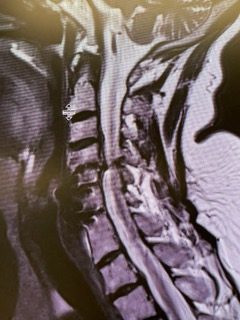

Current imaging studies (Figs. 1 and 2) demonstrated significant degenerative collapse of C45 segment, retrolisthesis and with severe right foraminal stenosis as well as C3-4 degenerative disc degeneration with moderate compression of thecal sac. Patient failed conservative management and it was decided, given her prior two anterior procedures, that an excellent decompression could be accomplished with a posterior laminectomy, foraminotomy and fusion to maintain alignment.

(Fig. 2) Axial T2 cervical MRI at C4-5 demonstrating significant osteophytic disease with bilateral neural foraminal compression of the C5 nerve roots, right greater than left.